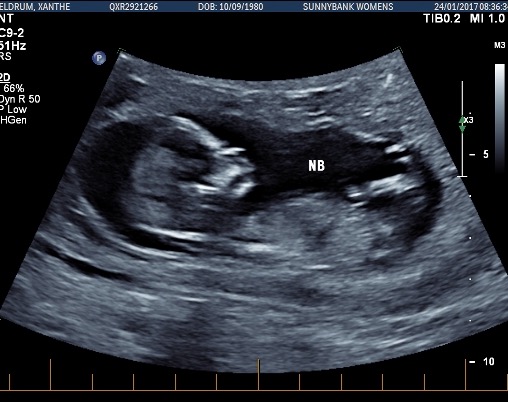

Hi all! I'd love some opinions here, I'm not even sure if there's a nub to see in any of these pictures. These were taken at exactly 13 weeks. I'm now 19 weeks and still have 1 week and 6 days until my anatomy scan (not that I'm counting or anything!) I have three boys and this is my last baby, so I'd love a little girl! Thanks in advance if anyone can help!

Attachment 35247